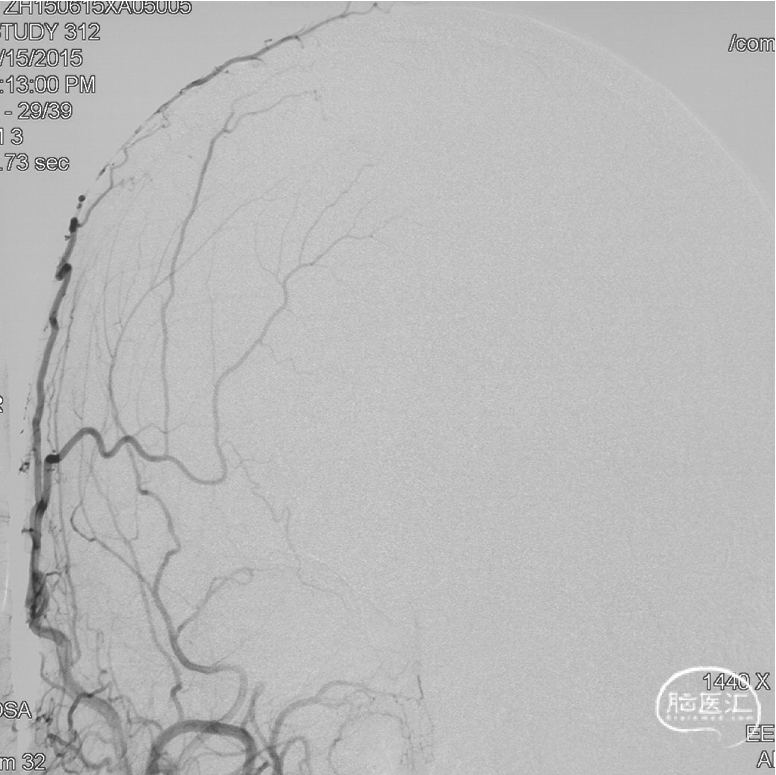

前颅窝底DAVF,由镰前动脉、双侧筛前、筛后动脉参与供血,通过皮层静脉向上矢状窦引流,引流静脉伴有瘤样扩张,Cognard IV型、Borden III型。由于脑膜中动脉-镰前动脉路径较为迂曲,超选困难,引流静脉迂曲扩张,预计到达瘘口起始端存在困难,决定经眼动脉-筛前动脉栓塞。

工作角度造影:黑色箭头为筛前动脉,白色箭头为筛后动脉,黄色箭头为镰前动脉,蓝色箭头为引流静脉起始部,红色箭头为视网膜中央动脉。拟通过眼动脉入路超选至筛前动脉进行栓塞。

Marathon微导管在Hybrid0.007微导丝导引下经左侧眼动脉超选至左侧筛前动脉,接近瘘口。

通过Marathon微导管超选造影,显示微导管楔入到靠近瘘口的动脉端。